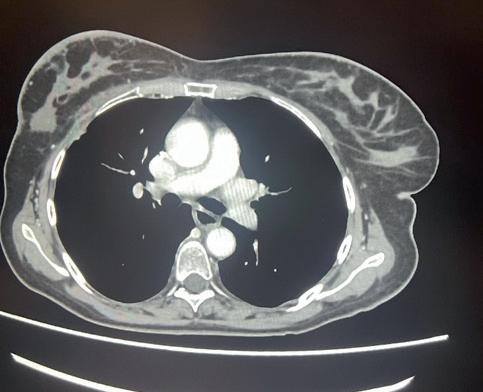

Tuttavia, nonostante la buona risposta iniziale, la TC total body con mezzo di contrasto del 28/12/2023 (figura 1) evidenzia progressione epatica ed encefalica con un quadro radiologico che mostra sovvertimento encefalico diffuso caratterizzato da numerose lesioni secondarie (almeno 10) a netta impregnazione contrastografica a sede sia cerebrale che cerebellare, prevalentemente subcentimetriche, la maggiore di 13 mm in nucleo-capsulare sx con nucleo necrotico e modesto alone edemigeno perilesionale.

La paziente, asintomatica sul piano neurologico e con marcatori tumorali negativi, viene sottoposta previo consulto multidisciplinare, a radioterapia panencefalica con risparmio dell’ippocampo con tecnica IMRT (30 Gy in 10 frazioni) e candidata poi a trattamento di II linea con T-DXd (5,4 mg/kg) q21, supportati dai dati di efficacia riportati dal DESTINY-Breast03, dalle analisi di sottogruppo degli studi DESTINY-Breast01, -02, -03 e dagli incoraggianti risultati preliminari degli studi DEBBRAH e TUXEDO-1.

La rivalutazione strumentale effettuata dopo 4 cicli di trattamento (figura 2) ha mostrato risposta intracranica completa ed epatica parziale. Lo studio della regione mammaria e ascellare con ecografia mammaria e mammografia ha mostrato assenza di lesioni infiltrative con presenza in sede retroareolare sx di un cluster di microcalcificazioni in assenza di linfoadenopatie ascellari. Lo studio tomografico con finestra per osso ha confermato la sovrapponibilità delle lesioni ossee rispetto alla precedente TC, in assenza di fratture patologiche. La paziente tuttora non ha mai manifestato eventi scheletrici secondari né riferisce dolore.